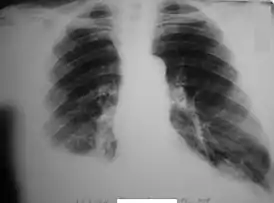

![]() Закрытые переломы VI, VII, VIII, IX рёбер справа. Правосторонний гемоторакс | |